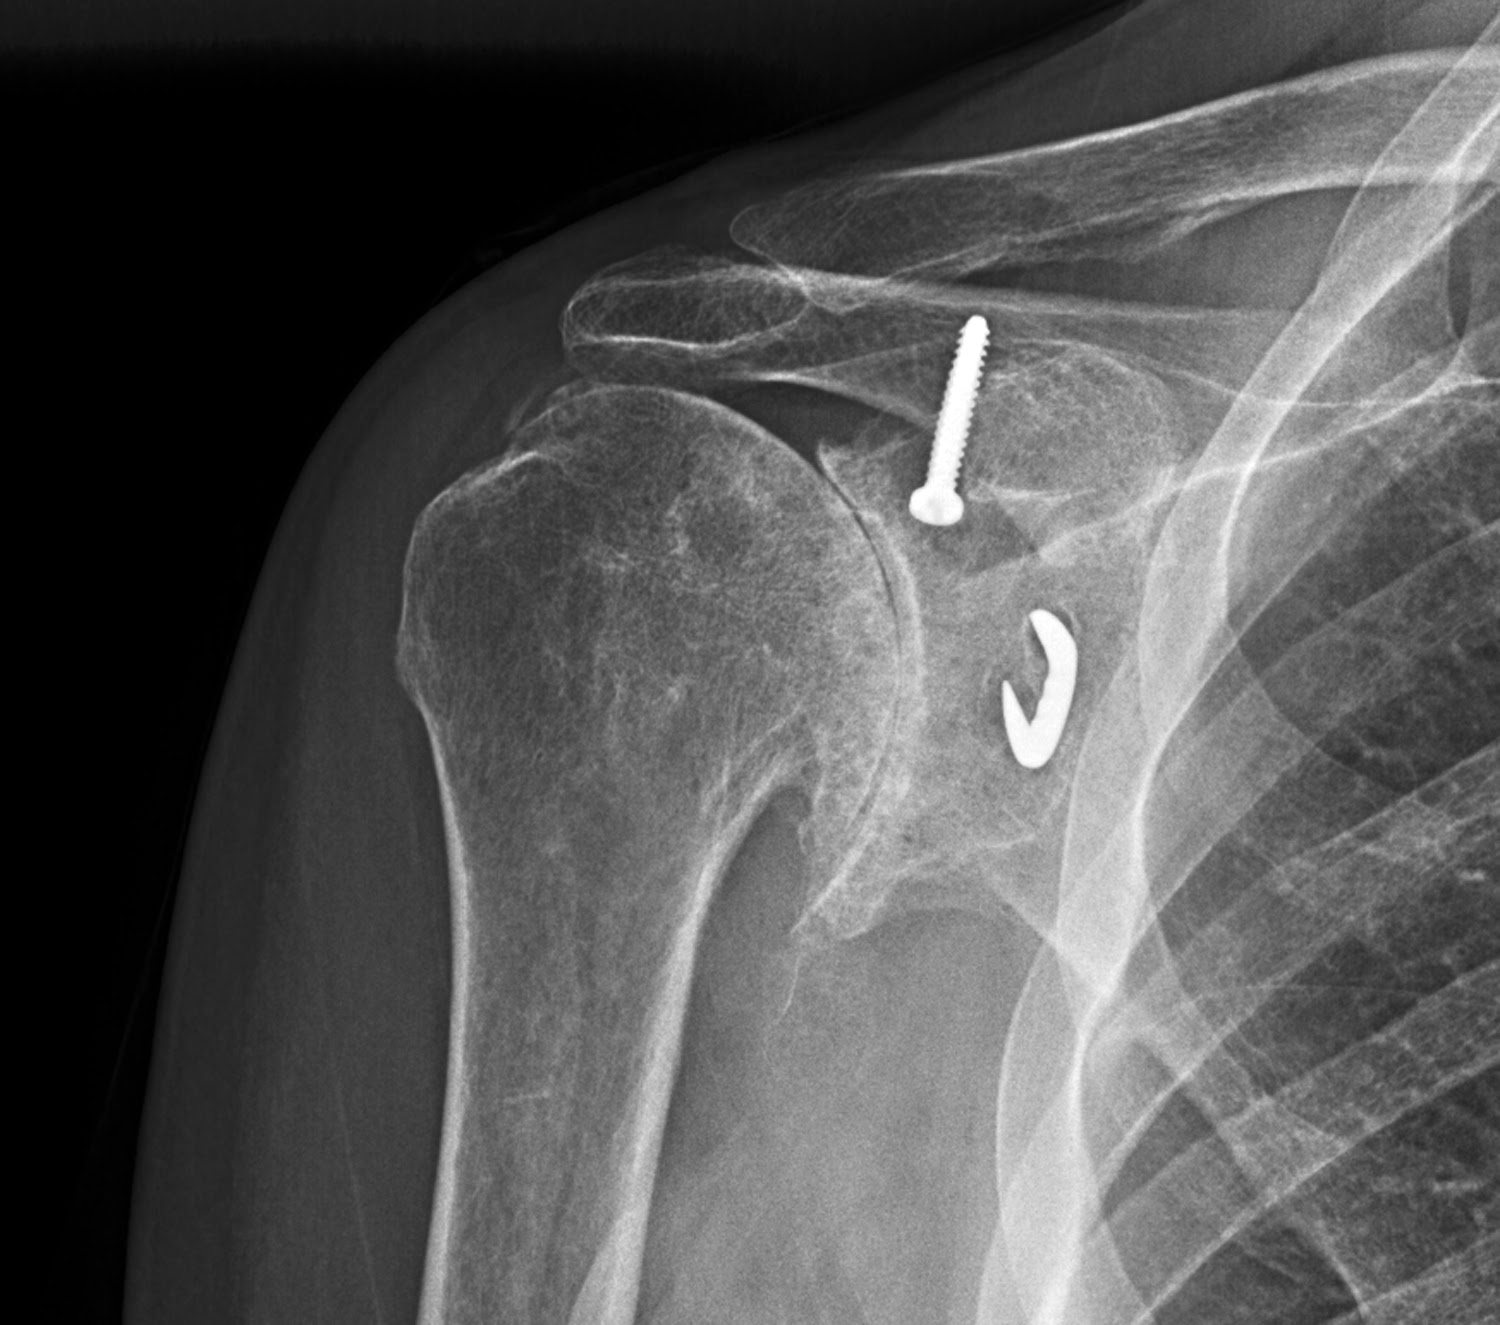

Фото артроза плечевого сустава

Ниже представлены фотографии, которые помогут вам лучше понять, как выглядит артроз плечевого сустава:

(Фото 1)